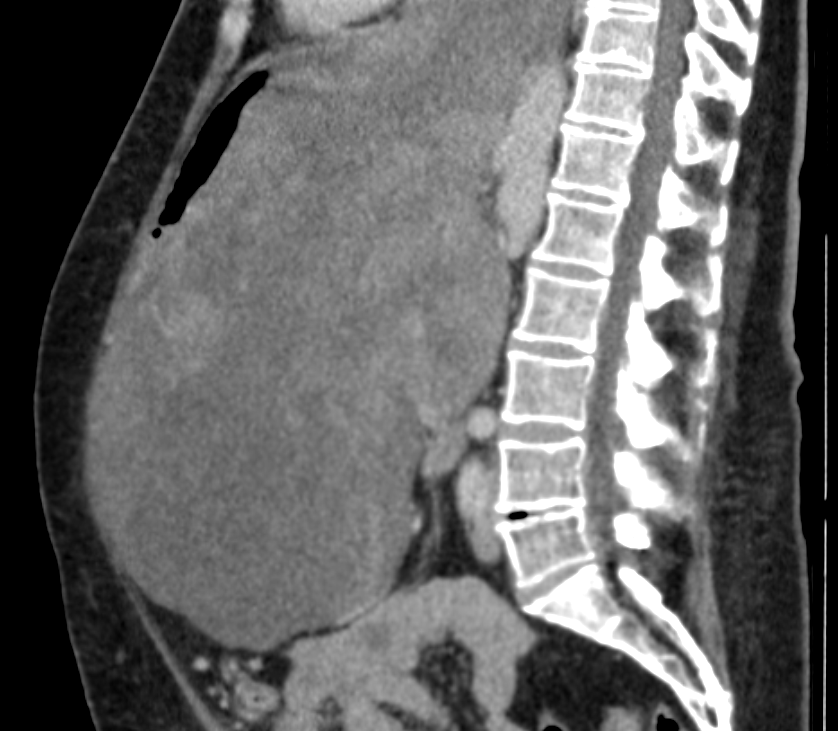

Beim Blick auf die Bilder aus dem Computertomografen mussten die Fachleute gleich zwei Mal hinschauen. Nicht etwa, weil das, was sie darauf sahen, so schwer zu entdecken war. Ganz im Gegenteil. Der Tumor, den sie auf dem Bild betrachten konnten, war derart groß, dass die Fachleute es kaum glauben konnten. Im Bauch der Patientin hatte sich ein 8,5 Kilogramm schwerer Tumor breitgemacht. Er war so groß geworden, dass er Organe wie Leber und Magen sowie den Darmtrakt an den Rand der Bauchdecke drängte. Durch eine Lücke im Zwerchfell ragte er sogar in den Brustkorb hinein. Im Klinikum Bremen-Mitte hat Prof. Dr. Hüseyin Bektas diesen rekordverdächtigen Tumor nun Anfang April in einer aufwendigen OP mit seinem Team entfernt.

Es war ein außergewöhnlicher Eingriff: Eine 8,5 Kilogramm schwere, bösartige Geschwulst stellte Prof. Dr. Hüseyin Bektas und sein Team vor eine ganz besondere Herausforderung. Die Patientin lebte monatelang mit besonders ausgeprägter Form von Magenkrebs, ohne dass sie es richtig bemerkte.

Bektas ist Chefarzt der Klinik für Allgemein-, Viszeral- und Onkologische Chirurgie im Klinikum Bremen-Mitte und hat in seiner langen Laufbahn bereits viele besondere Eingriffe erlebt. „Ein Fall mit einem Tumor dieser Größe war bisher noch nicht dabei“, sagt der Chirurg. Da der Tumor vom Magen aus auch schon Speiseröhre und Bauchspeicheldrüse befallen hatte, mussten diese teilweise – die Milz sogar komplett – mitentfernt werden. „Es war eine außergewöhnliche Operation für das gesamte Team“, sagt Bektas. Von dem großen Eingriff musste die Patientin sich zunächst erholen, am nächsten Tag folgte dann die Rekonstruktion des Magen-Darm-Trakts. So wurden dabei kleine Tumorreste entfernt und aus dem übriggebliebenen Magen ein Magenschlauch gebildet, der an die Speiseröhre angeschlossen wurde.

Was bei der Größe des Tumors fast unglaublich zu sein scheint: Die Patientin hatte bis vor wenigen Monaten mit dem Tumor gelebt, ohne ihn wirklich zu bemerken. Als es der 65-jährigen Frau dann zunehmend schlechter ging, sie kaum noch Nahrung zu sich nehmen konnte und so innerhalb von drei Monaten 22 Kilogramm abnahm, wurde sie von ihrem Arzt ins nächstgelegene Krankenhaus zur genaueren Diagnostik überwiesen. Mit dem dringenden Verdacht auf einen extrem großen Tumor wurde sie von dort aus dann an das Onkologische Zentrum des Klinikums Bremen-Mitte weitergeleitet, wo das Chirurgie-Team sie letztlich von dem riesigen Tumor befreite.